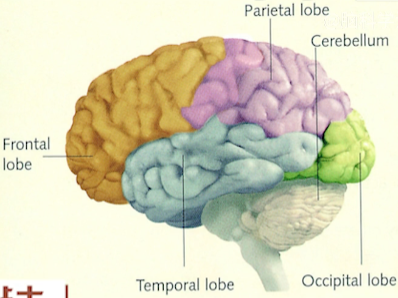

- 大脑结构图一

图1-1 - 前脑(黄色):计划、策略、情绪控制;

- 顶叶(紫色);

- 颞叶(灰色);

- 枕叶(绿色)。